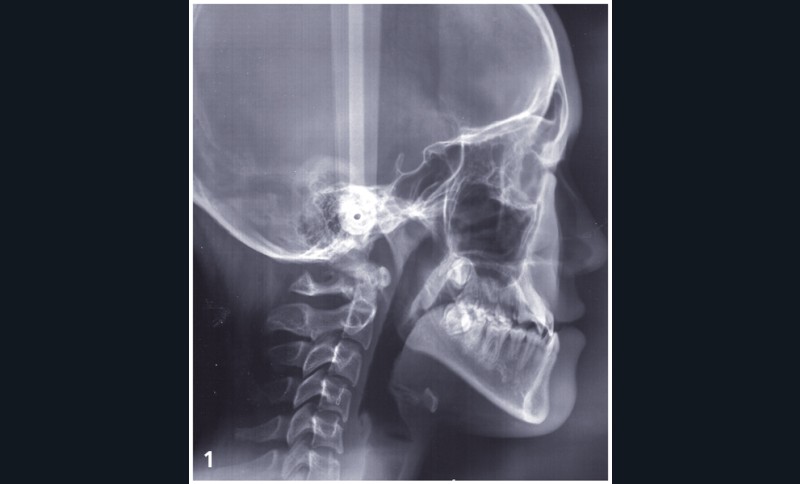

Sylvie se présente à l’âge de 15 ans avec une classe III squelettique (ANB -7,6°) d’origine maxillaire et mandibulaire sur un schéma facial à tendance hyperdivergent (FMA 31°) (fig. 1).

La classe III d’Angle et l’occlusion inversée s’accompagnent de signes de compensations alvéolo-dentaires : vestibuloversion des incisives supérieures (I/SN 114°) et linguoversion des incisives inférieures (IMPA 86°). L’encombrement à l’arcade maxillaire est important, souligné par des canines en infra-mésio-vestibulo-position.